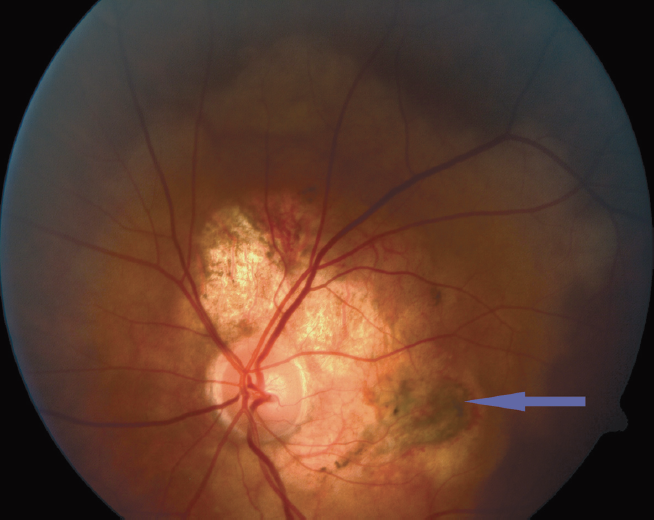

In two cases, the patients visited the clinic because of a decrease in their visual acuity (a decrease of 0.1 and 0.03, respectively, due to the formation of SNM in the macular zone). The patients were 22 and 35 years of age with binocular and monocular lesions, respectively. The patient with the binocular lesion (Fig. 6), exhibited a MCVA of 1.0 in his fellow eye. In this case, the patient had been noting a gradual decrease in his right eye visual acuity over the past 10 years, because of which he initially received inpatient treatment for central subacute chorioretinitis. Six months prior his visit to the Research Institute of Eye Diseases, a sharp decrease in his vision was noted, and, therefore, a SNM and a single intravitreal administration of anti-VEGF was prescribed.

Fig. 6. Right (a) and left (b) eye fundus photos of patient G., 22 years old, with bilateral choroidal osteoma. Arrow – choroidal neovascularization

Рис. 6. Фото глазного дна правого (а) и левого (b) глаза пациента Г., 22 года, с билатеральной остеомой хориоидеи. Стрелка — зона субретинальной неоваскулярной мембраны

In another case (Fig. 7), a 35-year-old female patient was diagnosed with a spot on her fundus during typical pregnancy examinations. The patient then noted a decrease in her vision the day after delivery. Six months before her visit to the Research Institute of Eye Diseases, fluorescence angiography was performed in another clinic, where she was diagnosed with peripapillary choroidal neovascularization, for which the patient received three intravitreal injections of the anti-VEGF drug.

Fig. 7. Fungus photo of patient N., 35 years old. Arrow – choroidal neovascularization

Рис. 7. Фото глазного дна пациентки Н., 35 лет. Стрелка — зона субретинальной неоваскулярной мембраны